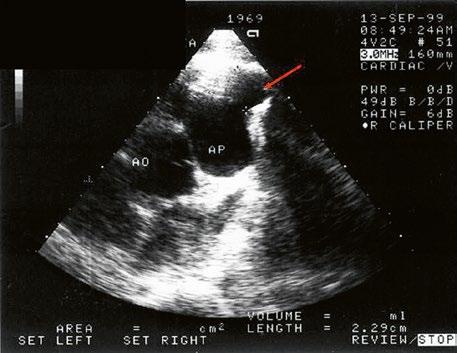

Izovaná PS je nejčastěji valvární, v dětství bývá stenotická chlopeň jemná, poddajná, se srůstem komisur a centrálním otvorem, cípy se v systole vydouvají (doming) (Obr. 45.36, Obr. 45.37). Asi v 15 % je chlopeň myxomatózně ztluštělá, dysplastická, rigidní, s málo pohyblivými cípy (typické pro syndrom Noonanové). V dospělosti dochází k degenerativním změnám a kalcifikaci abnormální pulmonální chlopně (Obr. 45.38).

Obr. 45.36 Valvární pulmonální stenóza, doming cípů, jemné cípy, srůst komisur (TEE, longitudinální projekce) AP – kmen plicnice, PK – pravá komora, PS – pravá síň

Obr. 45.37 Valvární stenóza plicnice, jemná chlopeň, doming cípů, TEE, longitudinální projekce, pacient s transpozičním postavením velkých tepen, aorta (AO) je vepředu, plicnice (AP) vzadu

Obr. 45.38 Fibrotická, ztluštělá, dysplastická pulmonální chlopeň se středně významnou valvární stenózou (šipka)

AO – aorta, AP – kmen plicnice, TTE, parasternální krátká osa na aortu